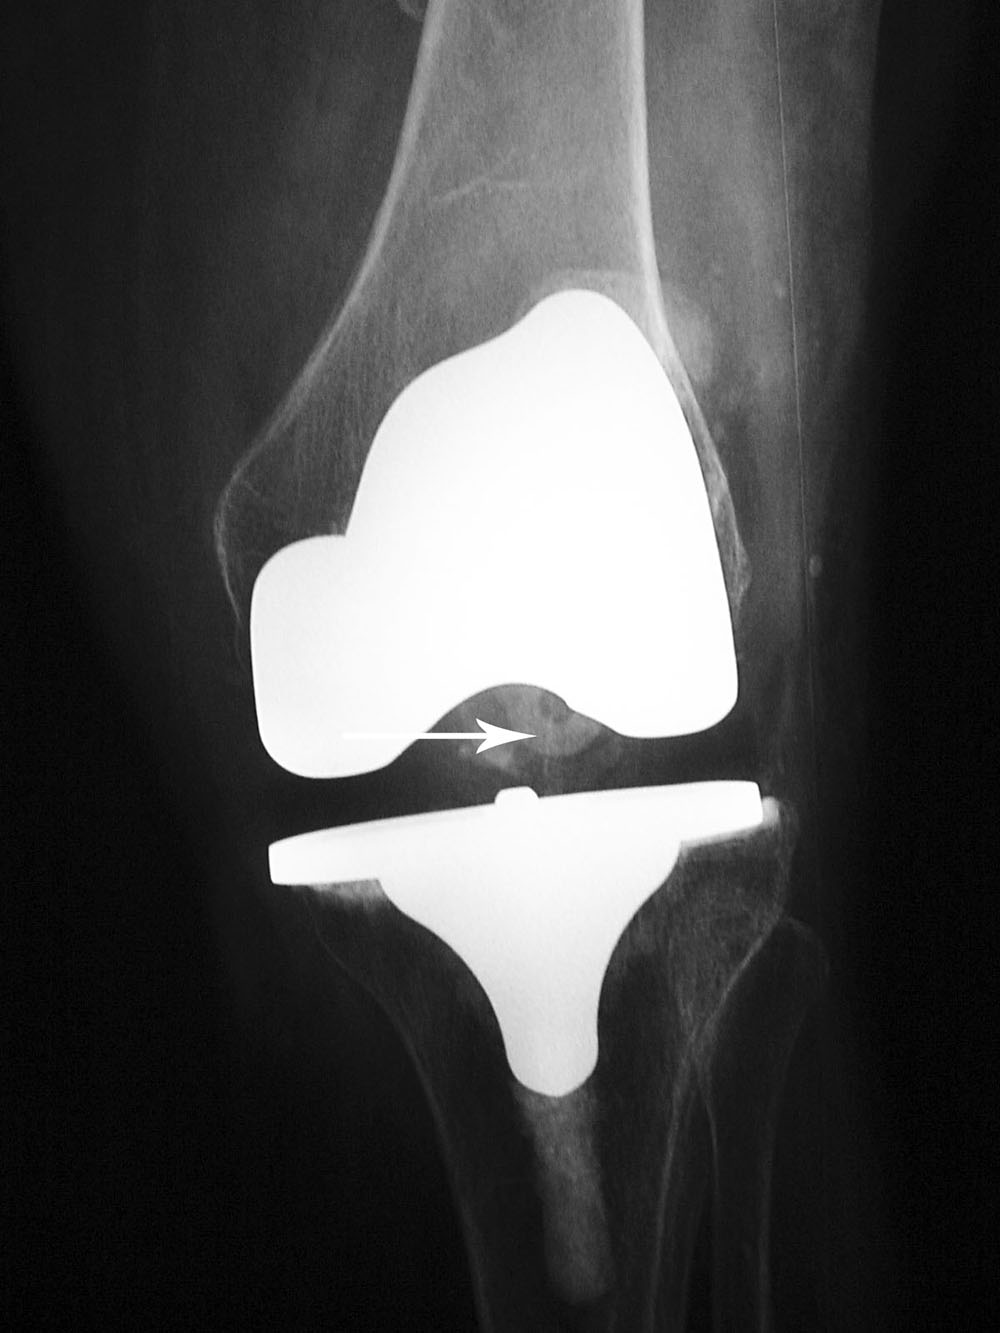

A posterior-stabilized knee or PCL-substituting knee has removal of the posterior cruciate ligament. This design limits posterior tibial translation in flexion. It contains a posterior cam, deeply dished articular surfaces, plus a third condyle or a central polyethylene post in the posterior middle portion of the tibial insert (figure: cruciate substituting TKA). In flexion this polyethylene post engages a transverse metal cam on the femoral component (Mulcahy, 2013). If the polyethylene post in the tibial insert does not have a metal backing it may not be visible on knee radiography. Usually one can differentiate cruciate-substituting from cruciate-retaining knee arthroplasty

on lateral views. The cruciate-substituting prosthesis often have a larger “box” or thicker femoral component.

| Posterior cruciate retaining total knee arthroplasty (TKA) |

Posterior cruciate substituting total knee prosthesis and patellar resurfacing. |

|